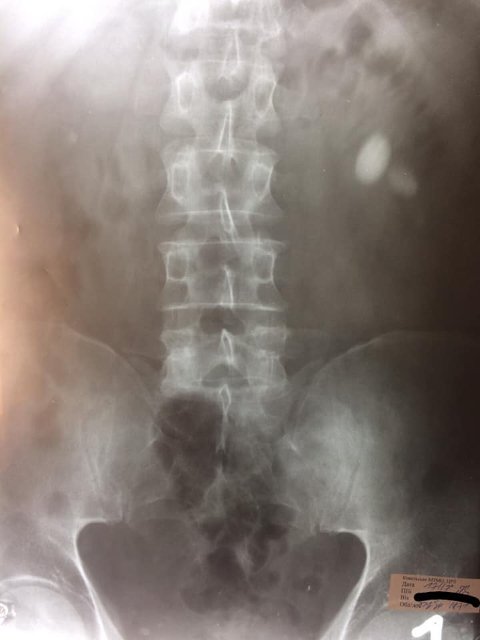

У центрі ендоурології Ковельського МТМО провели вдалу операцію з видалення каменю у нирках (черезшкірну перкутанну нефролітотрипсію).

Після стабілізації стану пацієнта урологи успішно видалили з лівої нирки 3 камені розміром 25 мм, 15 мм та 8 мм. У медзакладі зауважують, що для цього лікарям знадобився невеликий розріз довжиною лише 1 сантиметр. Операція пройшла комфортно та безболісно для пацієнта.